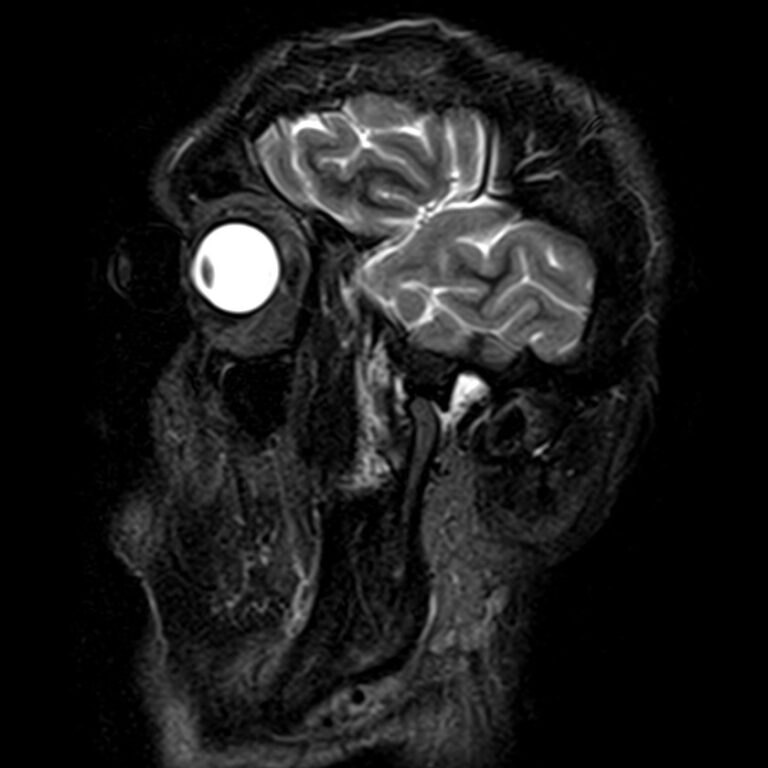

Височно-нижнечелюстной сустав является парным комбинированным суставом и имеет сложное строение. В него входят суставные ямки височной кости, суставные головки нижней челюсти и расположенные между ними хрящевые пластинки – мениски, выполняющие роль амортизаторов.

Чаще всего дисфункция височно-нижнечелюстного сустава обусловлена внутренним повреждением, смещением мениска и суставной головки нижней челюсти. Для определения степени смещения внутрисуставных структур выполняется функциональная проба с проведением МРТ в двух положениях:

Магнитно-резонансная томография является наиболее точным и эффективным методом диагностики поражения височно-нижнечелюстных суставов, так как позволяет получить детальную информацию о состоянии не только костей, но и связочного аппарата, хрящей, менисков, жевательных мышц, окружающих мягких тканей.

В клинике «Доступная медицина» можно пройти исследование МРТ височно-нижнечелюстного сустава на высокотехнологичном оборудовании. Клиника располагает новейшим томографом экспертного класса TOSHIBA VANTAGE TITAN 1,5 Тесла, который благодаря высокой индукции магнитного поля позволяет получать изображения исследуемой зоны в мельчайших подробностях. Томограф производит послойное сканирование области сустава и околосуставных мягких тканей, затем с помощью цифровых приложений преобразует полученные данные в трехмерные изображения превосходного качества.

При проведении магнитно-резонансной томографии на изображениях визуализируются: височная кость, головка мыщелкового отростка нижней челюсти, суставная щель. Помимо костных структур МРТ позволяет оценить состояние мягких тканей – внутрисуставного диска и связочного аппарата височно-нижнечелюстного сустава, жевательных мышц.

МРТ ВНЧС с капой включает в себя два протокола: с открытым ртом и с закрытым ртом. Данная функциональная проба позволяет проследить степень смещения внутрисуставных анатомических структур и оценить биомеханику движений в суставе.